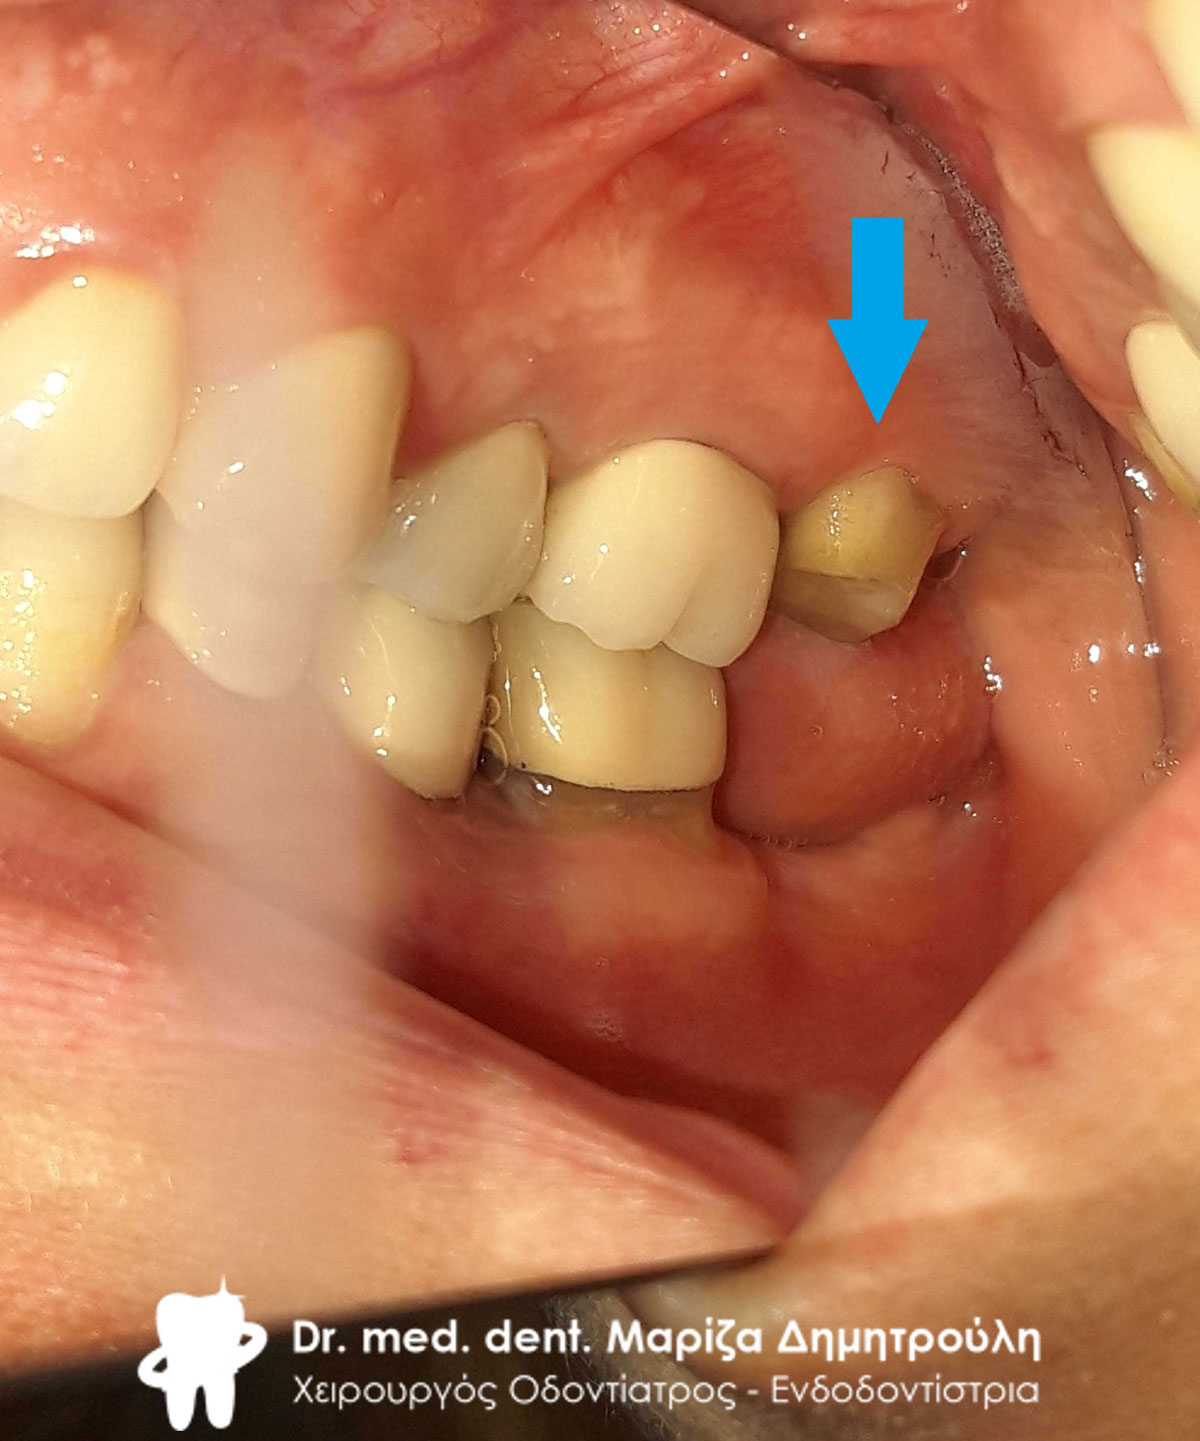

Αρχική κλινική εικόνα του μεγάλου οδοντικού ελλείμματος

Αρχική κλινική εικόνα του δοντιού με το παλιό μαύρο σφράγισμα αμαλγάματος